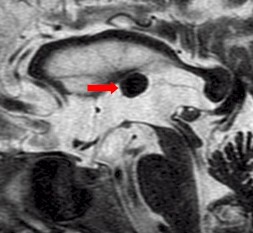

August 2005 - Colloid Cyst

Colloid cysts are benign, epithelial lined lesions, usually located antero-superior to the third ventricle (between the columns of the fornices). They supposedly originate due to an infolding of the neuroepithelium. These cysts may also occur in the choroid plexus of the lateral ventricles, subarachnoid space and brain parenchyma. They comprise approximately 2% of all glial neoplasms. Patients may present with headaches, sudden transient paralysis of both lower extremities, urinary incontinence, personality changes and/or dementia.

• On MRI

• These lesions may be either hypointense or hyperintense on either T1W or T2W images. The variability is due to it's contents. They may contain mucoid material, blood/hemosiderin, macrophages, cholesterol crystals, CSF and various ions (Na, Mg, Ca, Cu, Si, Al, Fe, P).

• Occasionally they may contain serous fluid and follow CSF signal characteristics.

• The lesions are thin walled and peripheral enhancement is common.